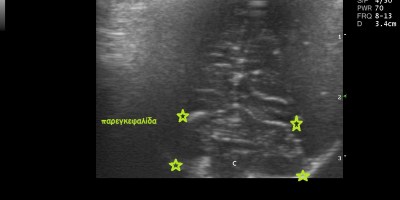

Brain Scan Hydrocephalus in Yorkshire Terrier/ ΥΔΡΟΚΕΦΑΛΙΑ ΣΕ ΦΥΛΗ YORKSHIRE TERRIER 25 Ιουνίου, 2014